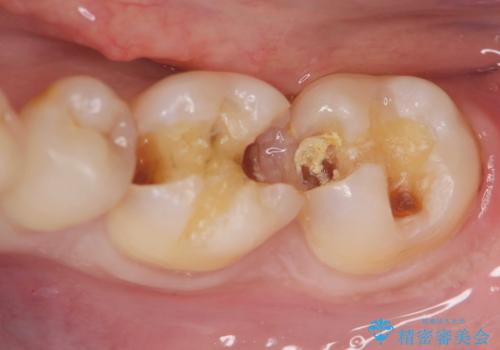

保険適応の白い詰め物レジンインレー下に再発した大きな虫歯治療

- 以前治療した歯の違和感、しみる感じの改善を求めて来院されました。

保険適応の素材、レジン素材による修復が行われていますが、X線写真より修復物の下には透過像(黒い影)が認められ、症状からも虫歯の再発が強く疑われます。